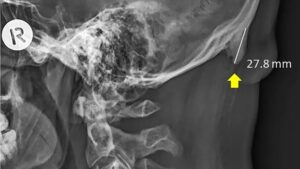

Nearly 30% of the 18-30 year old group had horns that were not within normal limits…over 10mm and up to 30mm. These findings correlated almost perfectly with patients who had FHP (Forward Head Protraction), aka Anterior Head Carriage. Usually, EEOP is more commonly found the OLDER we get…but for some reason this grouping of young patients had a higher prevalence than their age 50+ counterparts. This ultimately led the researchers to conclude that increased hand-held tech usage was to blame.